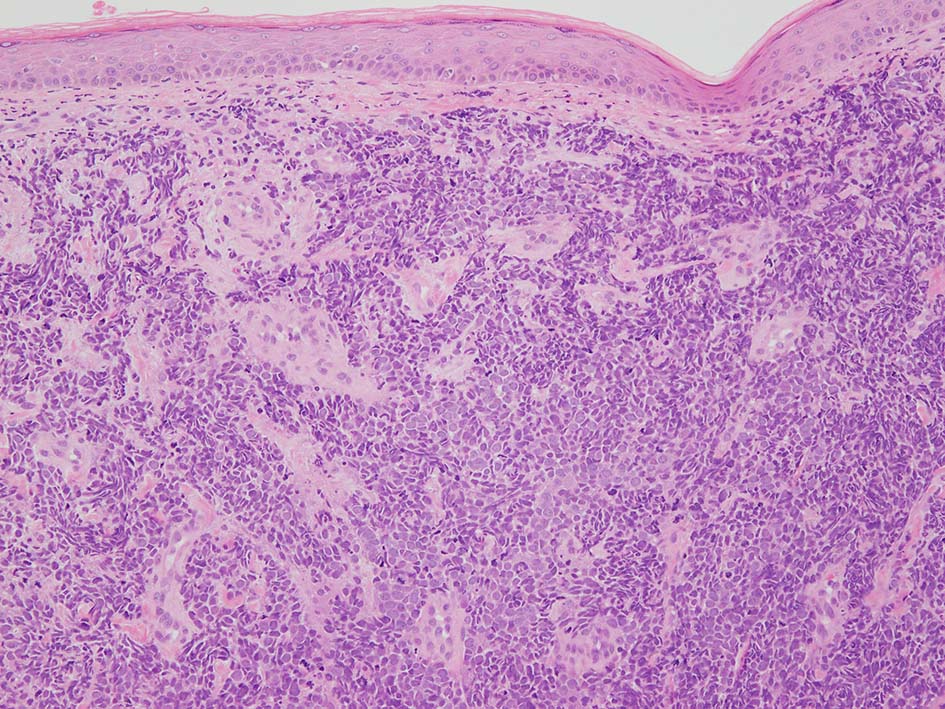

皮膚原発性Merkel細胞癌は 通常真皮を病変首座に増殖し, しばしば脂肪織まで浸潤する.

表皮とは連続性がなくGrenz zoneがみられるのが特徴であるが, 病理所見は多様であり, ときに表皮向性を示す症例やpagetoid patternを呈する症例もある.

下肢皮膚の赤色隆起性病変. 頂部の潰瘍部分より生検をおこなう.

loupe像 HE

血管を間質にしてround cellsが索状に増殖する所見. rossett様配列がある. CK20は特徴的な dot-like patternを示す. クリックで大きな画像が見られます.